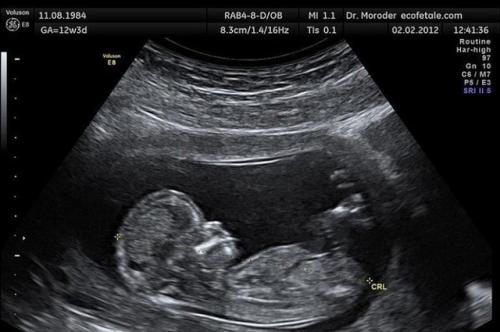

На 29 неделе беременности у женщины отошли воды, она была срочно доставлена в больницу. То, что началось дальше, повергло весь медперсонал в шок.

Во время операции кесарева сечения врач закричал:

"Почему не направили тебя на аборт? Куда смотрел твой гинеколог? " Продолжение в комментариях.